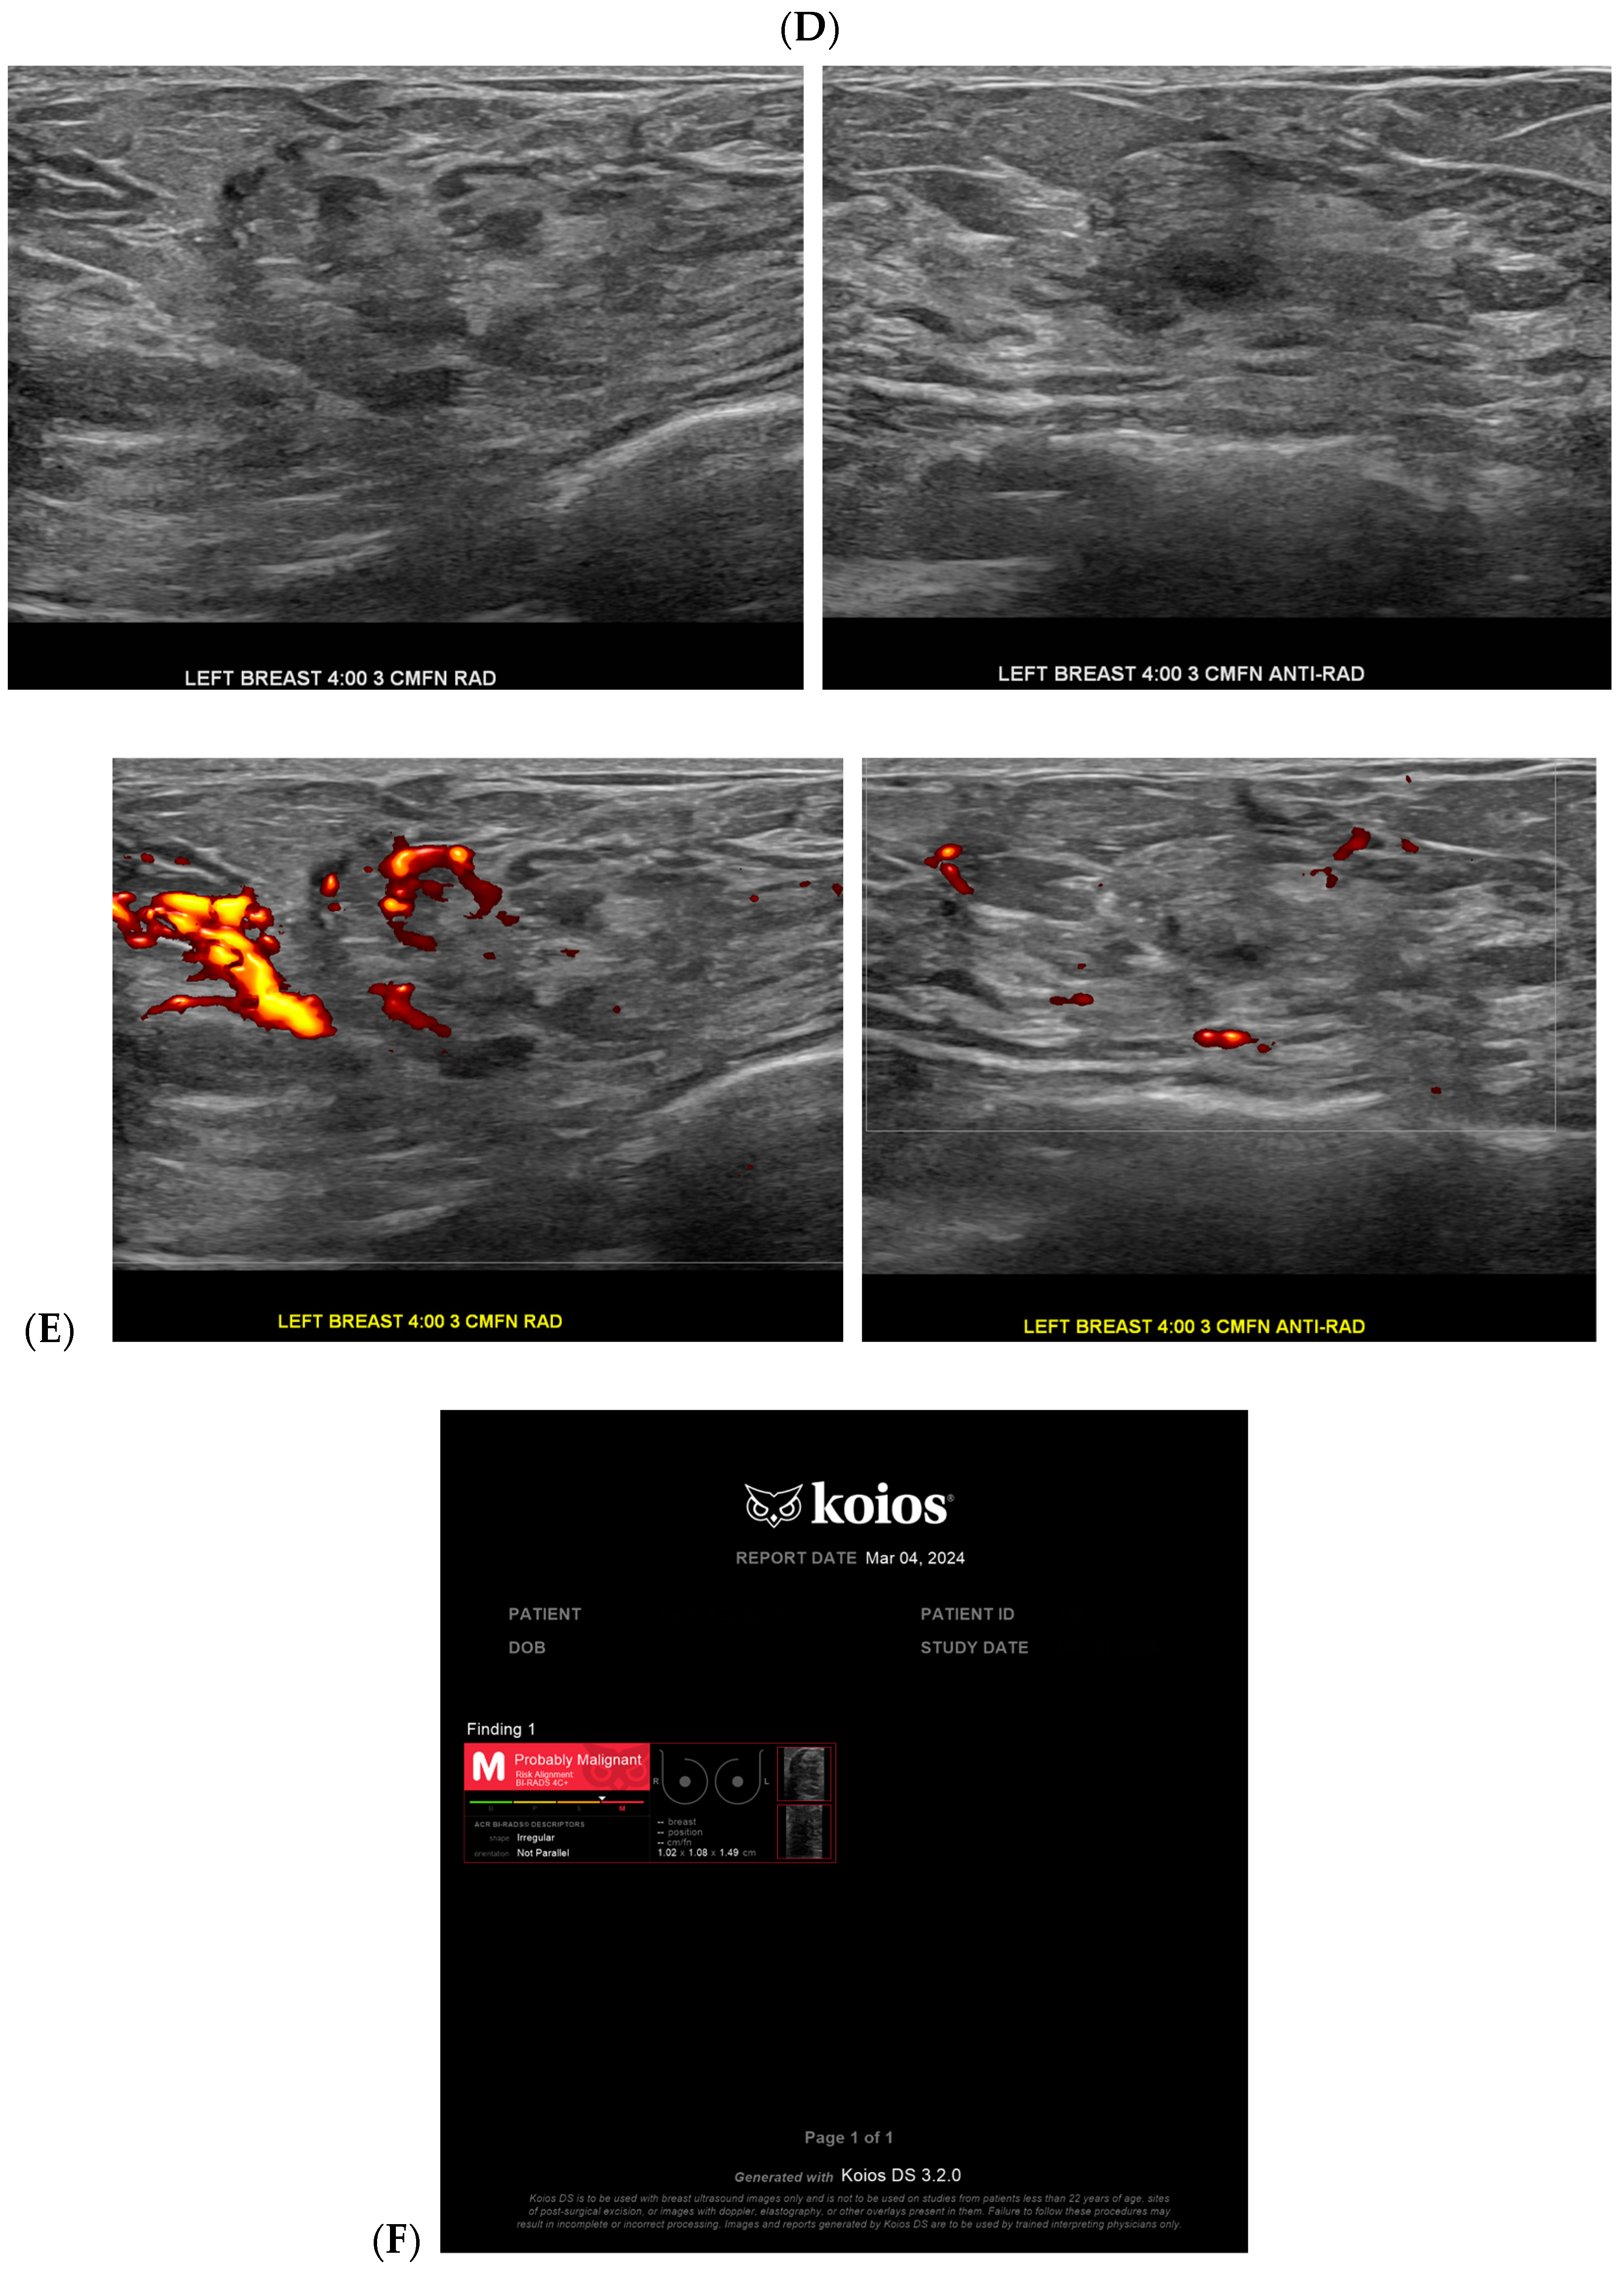

With the widespread implementation of DBT, which increases mammographic cancer detection sensitivity, there are larger volumes of images. This may ultimately increase the risk of reduced accuracy, perhaps due to reader fatigue and increased reading time [24]. There are numerous tomosynthesis AI products available, and at our institution we have implemented the use of Transpara, which is a deep learning-based AI system that uses deep CNN to help improve early-stage cancer detection and sensitivity (at similar specificity), while reducing reading time [24,25]. We view tomosynthesis AI as a valued asset to our clinical practice, as the software highlights potential areas of concern that require additional attention (Figure 1 and Figure 2). However, some areas flagged as concerning are often classically considered benign, such as stable post-lumpectomy sites, stable asymmetries and calcifications, or previously biopsied benign findings. That being said, tomosynthesis AI has been found to have a synergistic effect on cancer detection rate (CDR) when utilized by the radiologist. A study found that radiologist-only CDR was 67.3% and AI-only CDR was 72.7%, but when the radiologist and AI software were used together, the CDR increased to 83.6% [17,25,26]. Lunit INSIGHT MMG, Seoul, South Korea was the diagnostic support software used in this particular study [26].

Figure 1.

Developing asymmetry detected by artificial intelligence (AI): Between the baseline screening mammogram (A) and the follow-up screening mammogram 17 months later (B), there has been a very subtle development of left breast asymmetry that is difficult to perceive with the naked eye. However, the AI program Transpara highlighted potential regions of interest (C) for the radiologist to query for additional mammographic and sonographic imaging. On further diagnostic imaging, the subtle asymmetry corresponds to a hypoechoic mass at left 4:00, 3 cm FN (D) with hypervascularity (E). AI program Koios correctly recognized the mass as “Probably Malignant”, and this area returned as a biopsy-proven invasive malignancy with lymphangitic spread (F). Images obtained from the Icahn School of Medicine at Mount Sinai.

Cancer detection systems typically involve neural networks, machine learning, or deep learning developed from training models to recognize patterns, while diagnostic systems use an additional algorithm to classify [17]. Several CNN models have been developed to correlate ultrasound imaging features of a lesion with the four-classification breast cancer molecular subtypes [42]. Our institution uses Koios, which utilizes machine learning and AI to generate the probability of malignancy of a breast finding by evaluating a region of interest (ROI) selected by a radiologist [3,5]. Ultrasound AI has been found to reduce intra- and interobserver variability and to improve accurate BI-RADS classification of sonographic breast findings [3,5]. Ultrasound AI can also increase CDR [5] and reduce the number of unnecessary biopsies [5,43,44] (Figure 1, Figure 3, and Figure 4).